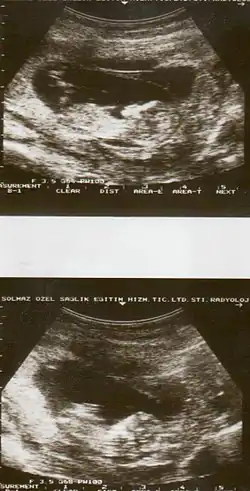

| Diagnostic method | Based on symptoms, ultrasound[1] |

The cause of placental abruption is not entirely clear.[2] Risk factors include smoking, pre-eclampsia, prior abruption (the most important and predictive risk factor), trauma during pregnancy, cocaine use, and previous cesarean section.[2][1] Diagnosis is based on symptoms and supported by ultrasound.[1] It is classified as a complication of pregnancy.[1]

Placental abruption is suspected when a pregnant mother has sudden localized abdominal pain with or without bleeding. The fundus may be monitored because a rising fundus can indicate bleeding. An ultrasound may be used to rule out placenta praevia but is not diagnostic for abruption.[8] The diagnosis is one of exclusion, meaning other possible sources of vaginal bleeding or abdominal pain have to be ruled out in order to diagnose placental abruption.[5] Of note, use of magnetic resonance imaging has been found to be highly sensitive in depicting placental abruption, and may be considered if no ultrasound evidence of placental abruption is present, especially if the diagnosis of placental abruption would change management.[16]